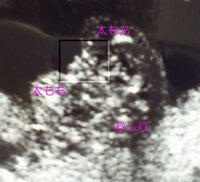

そして、胎児が成長してくると、 陰茎の根本に陰嚢が2つ確認できる ようになります。 女の子は陰茎のような目立つ外性器がないので判定が難しいのですが、 太ももの間に木の葉やコーヒー豆のような大陰唇が見え ます。 特徴がつかみにくい女の子ですが、妊娠週~24週 (妊娠6ヶ月から7ヶ月)頃になると、赤ちゃんのお尻を下からのぞいたような以下の画像のように、ようやく判明するケースが多いです。 この頃になると 女の子の赤ちゃんは、子宮と膀胱が2つの黒い点となっ